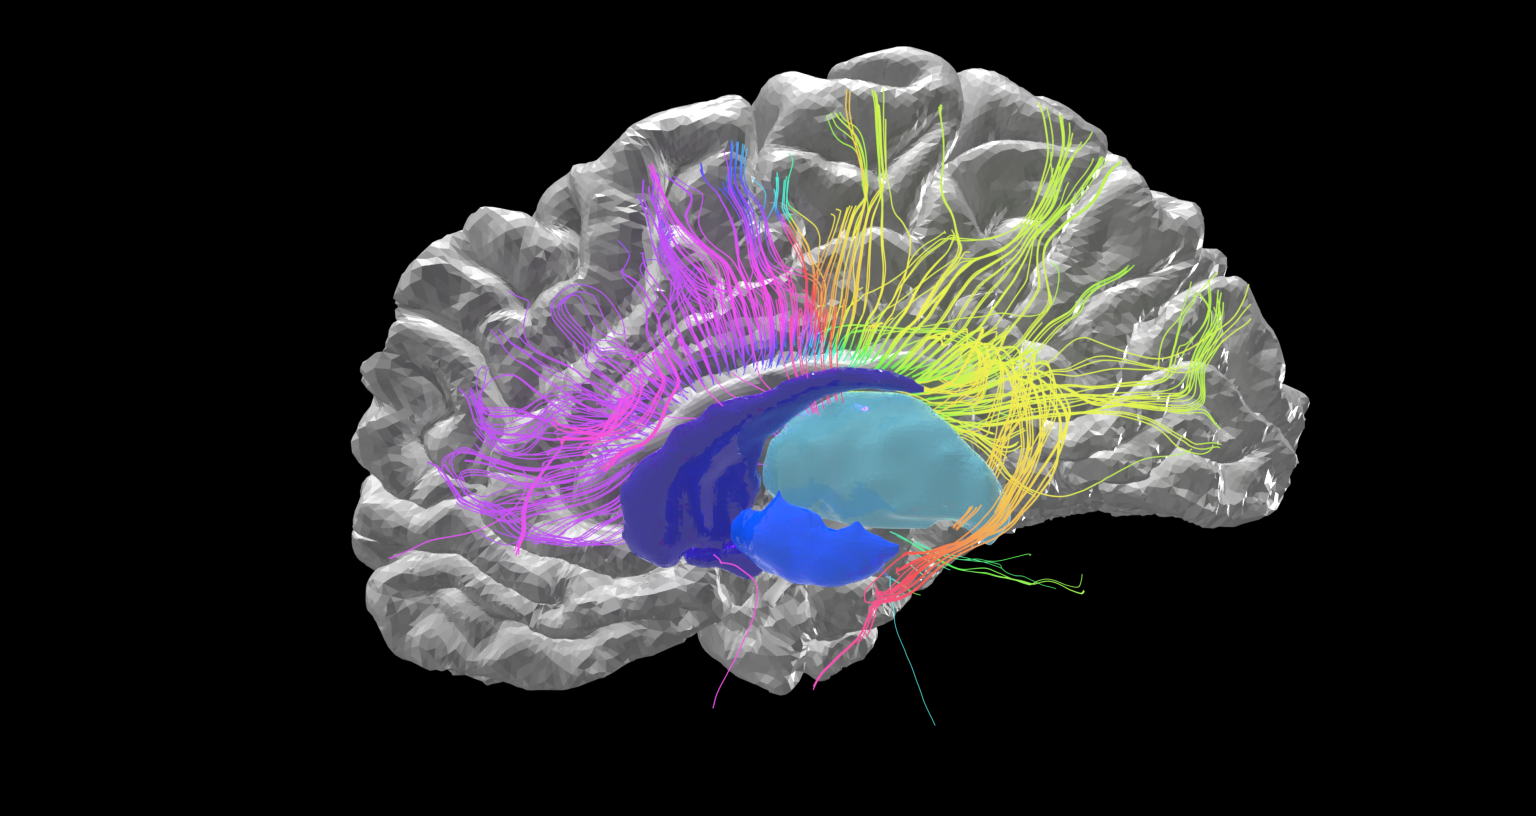

mri brain scan alzheimer using space imaging human software scans wikipedia identifying esa researchers hypothalamus applications pillars medical wiki thalamus

brain scan stroke mri dementia advanced analysis predict related help may mehar pranjal

Mri brain scan alzheimer using space imaging human software scans wikipedia identifying esa researchers hypothalamus applications pillars medical wiki thalamus. Brain scans scan cte concussion athletes football may concussions mainichi nfl players reveal living damage after shows april former boston. Brain mri scan coloured sagittal geoff tompkinson se photograph like numbers brains drips vitamin peddling doctors pointless stressed when look